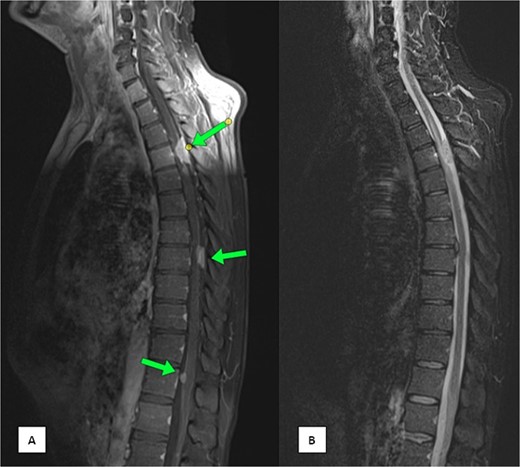

The patient underwent three cycles of chemotherapy, achieving near-complete metabolic resolution of the nasopharyngeal mass, regression of lymph nodes, and resolution of liver and humeral lesions. Subsequently, he completed 33 fractions of radiotherapy. Post-treatment PET-CT showed no recurrence but revealed focal increased fluorodeoxyglucose (FDG) uptake at spinal cord levels T4 and T8, necessitating magnetic resonance imaging (MRI) evaluation. MRI identified dorsal intraspinal enhancing soft tissue lesions indenting the spinal cord (Fig. 1), consistent with dural-based metastases.

MRI of the spine (A) sagittal T1-weighted fat-saturated post-contrast image and (B) sagittal Short Tau Inversion Recovery (STIR) sequence demonstrating multiple intra-spinal, extra-medullary meningeal-based enhancing lesions. The largest lesion measures 22 × 11 mm at the D4 level.